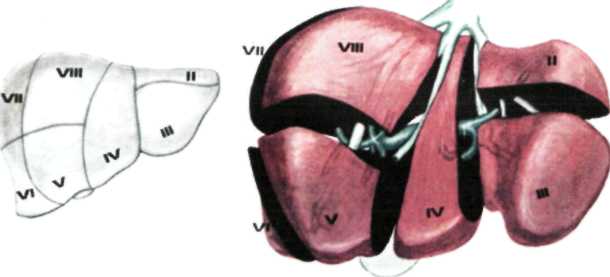

В печени различают две доли (правая и левая) и 8 сегментов. Границей между правой и левой долями является плоскость, проведенная через ямку желчного пузыря. Учитывая архитектонику внутрипеченочных сосудов (из них главные - это ветвление воротной вены) и желчных протоков, каждая доля в свою очередь делится на 4 сегмента: левая доля состоит из первых четырех сегментов.

Правая доля включает остальные 4 сегмента) (рис.1.25).

Рис.1.25. Сегменты печени